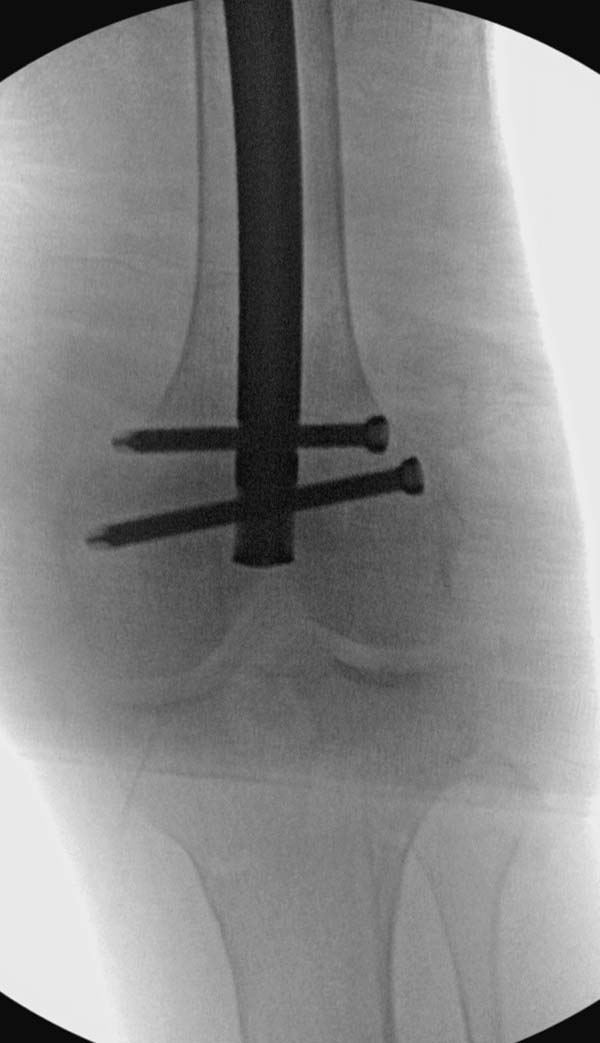

остаться до конца лечения, начал изучать язык... Для облегчения

транспортировки на второй день после поступления правая сторона была

фиксирована ретроградным гвоздем.

Теперь по серьезному. Учитывая качество кости и низкий гемоглобин,

периодический гемодиализ и воодушевленный результатом выступлении

Челнокова, вместо пластины решил попробовать гвоздь. Но жесткие FDА

условии не позволяют воспользоваться дивайсом до получения разрешения на

пользование.

Гвоздь из ретроградного гвоздя DePuy в 15 мм получился немного тоньше,

чем у Российских коллег.

Операция не обошлась без казуса, при подготовке гвоздя произошла ошибка

в расчете. Пришлось коррегигировать по ходу операции, где длинный

дистальный отдел гвоздя срезали во время операции.

А так вроде первый американский опыт прошел удачно. У больного низкий

гемоглобин, который подправили во время операции переливанием крови.

надеюсь, контрагированные мышцы сохранит длину конечности. Контрольный

снимок показал устойчивую фиксацию.